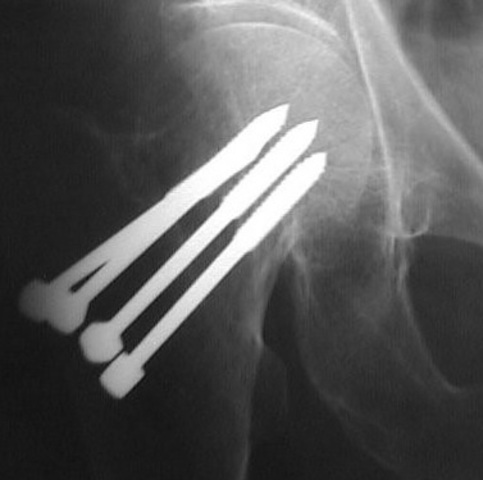

• Fractura Subcapital, lado derecho.

• Tratamiento Osteosintesis con clavos de Knowles

• Al año, hay consolidación de fractura completa

Cabeza femoral estaba parcialmente necrosada y luxada medialmente.

• Después de la valoración se implanta una prótesis total segmentada

Con restos de cabeza femoral troceada como injerto triturado y compactado en el fondo de la cavidad acetabular.